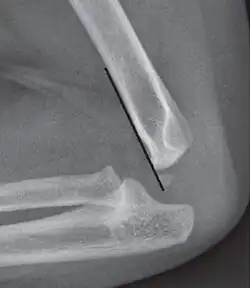

Fish-tail sign - The distal fragment is rotated away from the proximal fragment, thus the sharp ends of the proximal fragment looks like a shape of a fish-tail.[8]